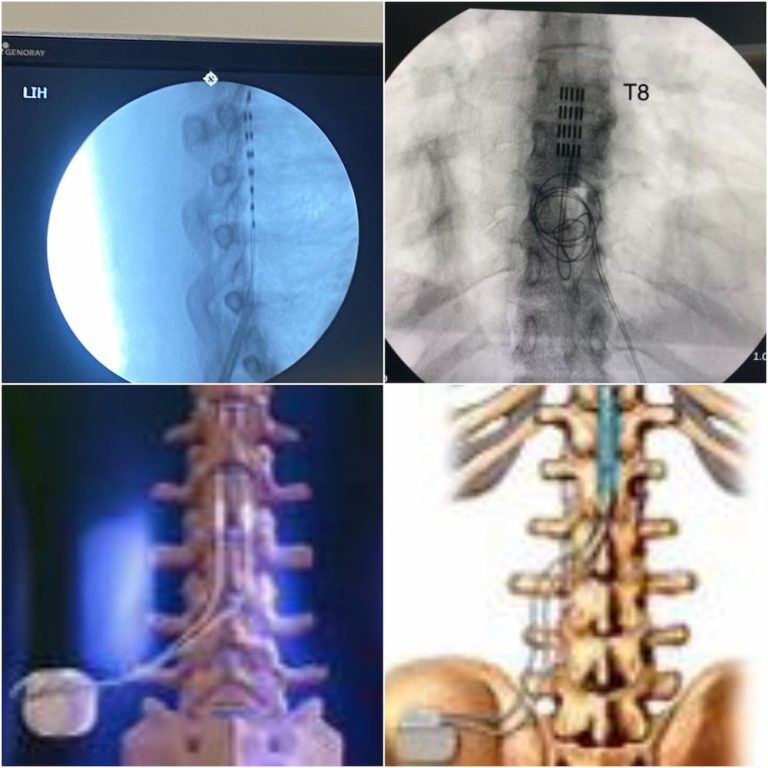

The procedure for implanting a spinal cord stimulator typically involves two stages: a trial period and the permanent implantation. During the trial period, temporary leads are inserted into the epidural space of the spine under local anesthesia, and an external stimulator is used to test the effectiveness of the therapy. This trial period usually lasts about a week. If the patient experiences significant pain relief, the permanent device is implanted. This involves placing the permanent leads in the same location and implanting the stimulator device under the skin, usually in the lower back or abdomen. The entire procedure is minimally invasive and usually performed on an outpatient basis. Patients can typically return home the same day and resume normal activities after a short recovery period.